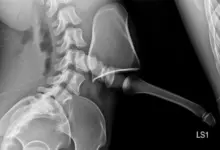

Exames que confirmam

O caminho começa com história clínica e exame físico detalhados. Em seguida, os exames de imagem definem o grau e estabilidade.

- Radiografias AP e perfil, com medidas de Meyerding e dos ângulos.

- Radiografias dinâmicas em flexão e extensão, para avaliar a instabilidade.

- Tomografia, útil em dúvidas anatômicas e planejamento cirúrgico.